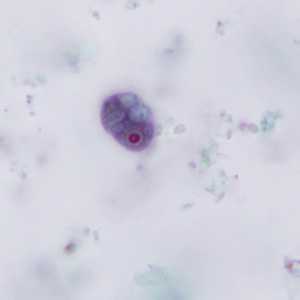

E. nana trophozoites stained with trichrome.

Figure A: Trophozoite of E. nana stained with trichrome.

Figure B: Trophozoites of E. nana stained with trichrome.

Figure C: Trophozoite of E. nana stained with trichrome.

Figure D: Trophozoite of E. nana stained with trichrome. Image courtesy of the Kansas Department of Health and Environment.

Figure E: Trophozoite of E. nana stained with trichrome.